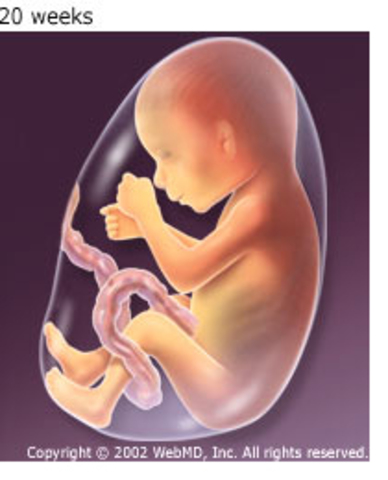

• Period: to

Length and Weight at Month 6

Going from head to heel, the baby is now 11.8 inches long and weighs 1.32 pounds.